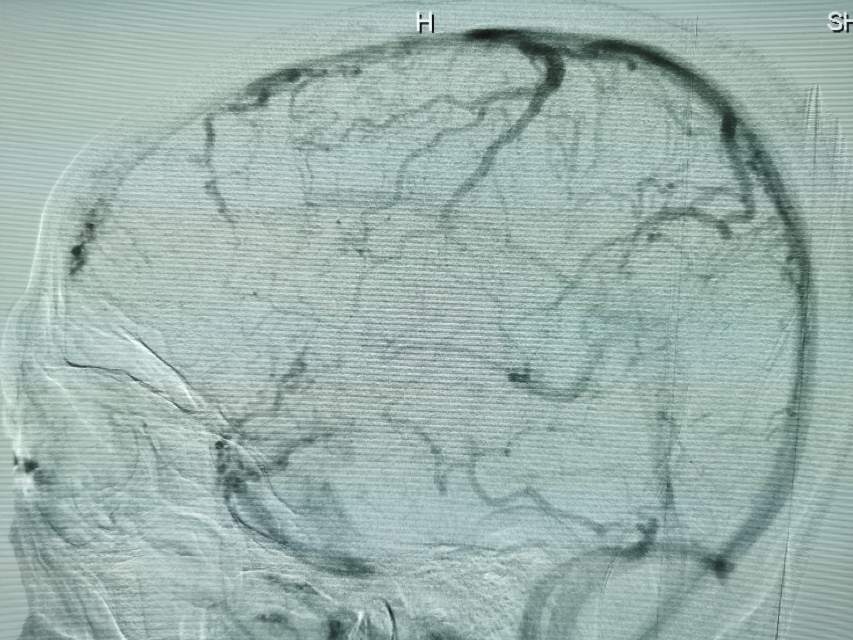

鉴于老人家体质虚弱,走路不方便,疫情期间,家人又不方便陪同,我们采用最微创的远侧桡动脉入路为老人家做了进一步检查,血管真的很扭哈,老人家也听不清楚,检查期间动来动去的,结果发现:下水道(深浅静脉系统有血栓堵塞)不通畅哦,次日给予了药物调整。治疗3天后,老人家听力明显改善,可以和医生自由交流,下床走路也如履平地,完全换了一个人哈~~~